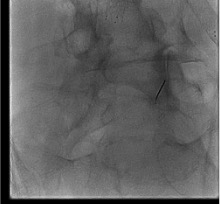

Contrast arthrogram

Contrast check

Contrast spreads widely / epidural pattern instead of intra-articular

Likely cause: Needle tip through posterior joint capsule into epidural or paraspinal space; or existing capsular defect from prior injections.

Next step: Withdraw needle to re-enter joint proper. If a capsular defect allows medication to track epidurally, reduce volume to 1 mL total. Document the finding — epidural spread may still be therapeutic but the procedure is technically a pericapsular injection.